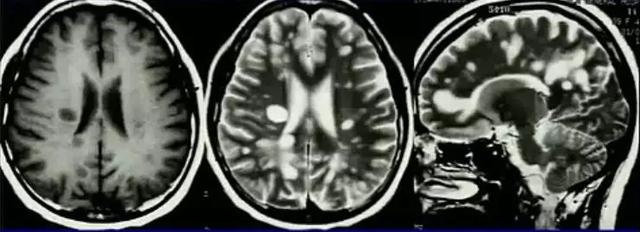

同心圆硬化:可能为 MS 的一种特殊类型,好发于 20-50 岁,平均 30 岁,男性略多,无家族史/感染史,急性/亚急性起病,半数有低热、乏力、头痛等先驱症状,1-3 周症状达顶峰

首发多为性格或行为改变:交往困难、情感淡漠、沉默寡言少语、头痛头晕乏力,CSF 压力可增高,蛋白或细胞略升高,可出现少量红细胞

CT:脑白质去有洋葱头或年轮样黑白相间的类圆形环带,增强后洋葱头样结构更加明显。MRI 上脑白质可见急性期双重构造病变及亚急性期的同心圆层状改变

病理:脱髓鞘病灶分布不连续,呈板层样同心圆改变(脱髓鞘与髓鞘保留区相间,即脱髓鞘病变区与正常脑组织呈年轮样交替排列),小静脉周围有淋巴细胞为主的炎细胞浸润,同时在髓鞘破坏后有神经胶质增生,所以称为同心圆硬化。